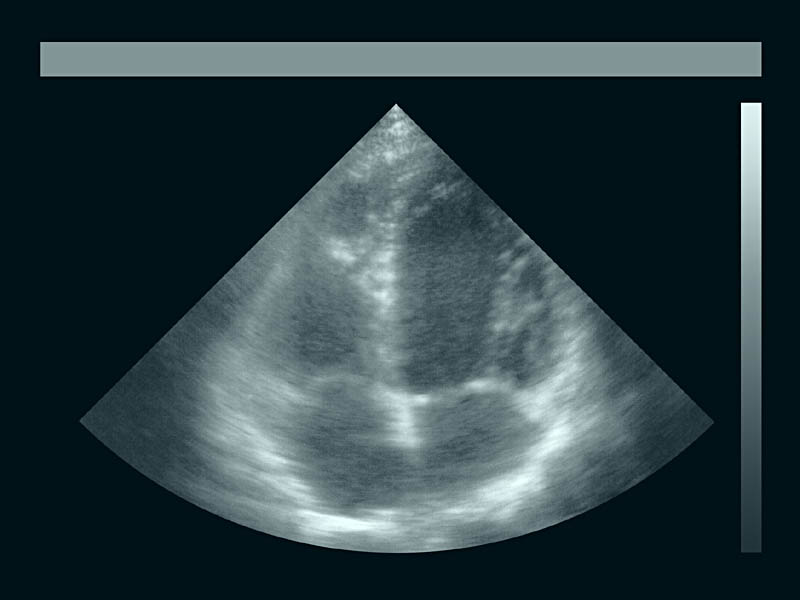

Herz-Seitenansicht

Melitta Moschik HUMAN INTERFACE 2001

Sono-/Computergrafischer Film

je 60 x 80 x 12 cm